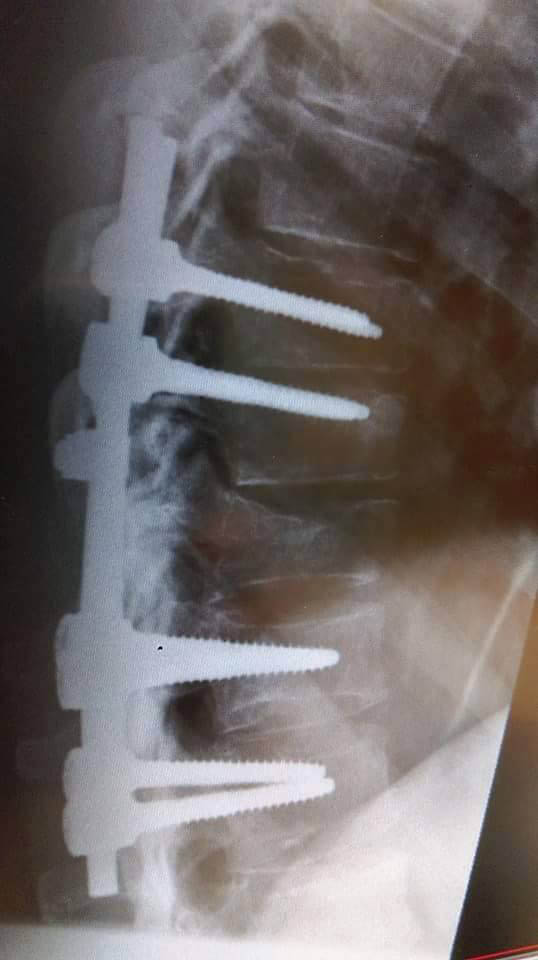

Mr Tighe spent three months in a rigid full back and chest brace and has extensive metalwork supporting his damaged spine.

“Running is one thing that really hurts. The mechanics of having five spinal vertebrae that are now internally scaffolded together with screws and bars isn’t really a good feeling. I’m told that taking up running in the long term is not something that will benefit me due to the impact and lack of flexibility and shock absorption.